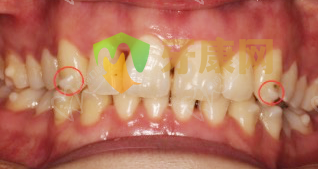

首先大家可以看圖,紅色圓圈標記的白色“小凸起”就是附件,它的作用是:

1. 增強固位。把牙套更好地固定在牙齒上,使牙套與牙齒的貼合更緊密。

2. 加強牙套對牙齒施力。更好地控制矯治力方向,讓牙套更精準地控制牙齒的移動。

附件設計是否合理,粘貼是否到位,與牙面及牙套的貼合度,是會影響矯正時長和效果。